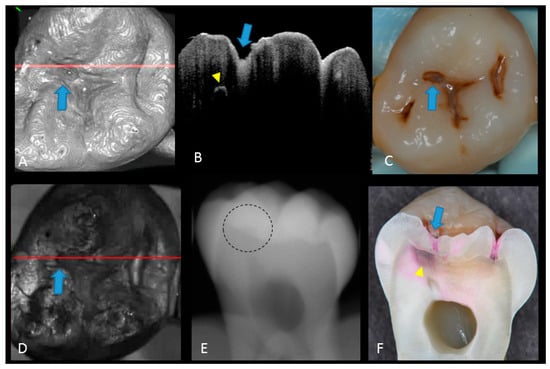

2. Materials and Methods

2.1. Specimen Preparation

2.2. Photography and X-ray Imaging

2.3. Optical Coherence Tomography

2.5. Validation of the Actual Scores